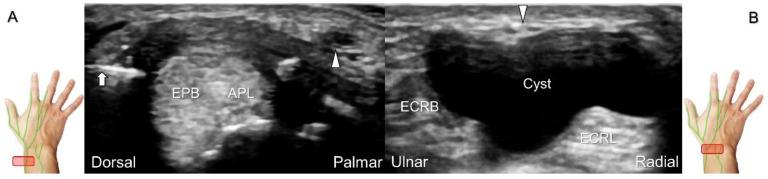

超声已成为一种极具价值的工具,用于腕部区域周围神经病变的成像,特别是对于诸如腕管综合征和尺神经管综合征等常见病症。大量研究表明,神经在卡压部位近端肿胀、边界不清和平扁是神经卡压的特征。然而,关于腕部和手部的小神经或终末神经的信息却很匮乏。本文旨在通过全面概述这些神经卡压的扫描技术、病理学和引导注射方法来填补这一知识空白。本综述详细阐述了正中神经(主干、掌皮支和返支)、尺神经(主干、浅支、深支、掌尺皮支和背尺皮支)、桡浅神经、骨间后神经、掌总/指固有神经和背总/指固有神经。一系列超声图像用于详细说明这些技术。最后,超声检查结果补充了电诊断研究,有助于更好地理解整个临床情况,而超声引导下的干预措施对于治疗相关神经病变是安全有效的。